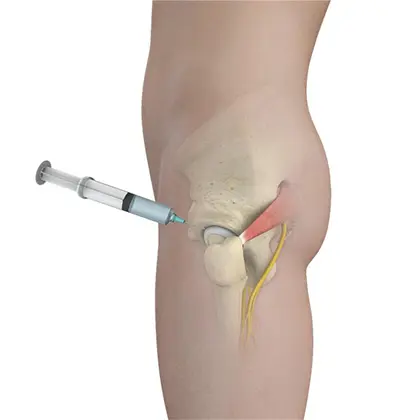

- Diagnostic Injection: A local anesthetic may be injected to confirm the source of hip pain

- Regenerative medicine injections, such as platelet-rich plasma (PRP) or bone marrow aspirate concentrate (BMAC), to support healing